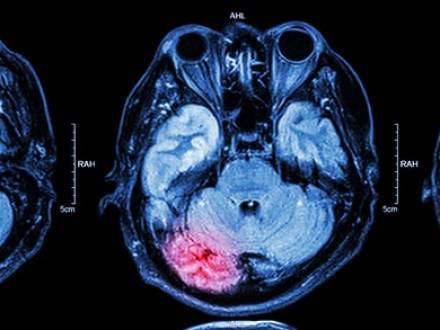

If an injury causes long-term or permanent damage to a person’s body or mind, it is catastrophic. These injuries can prevent victims from returning to work or living independently. Examples of catastrophic injuries include spinal cord injuries, partial or total paralysis, multiple fractures, traumatic brain injuries, loss of limbs, and severe burns.

Catastrophic injuries usually require emergency treatment, surgeries, rehabilitation, and sometimes lifelong care. A permanent disability could mean that you need to modify your vehicle or home. The physical, emotional, and financial toll can be overwhelming for both you and your family.